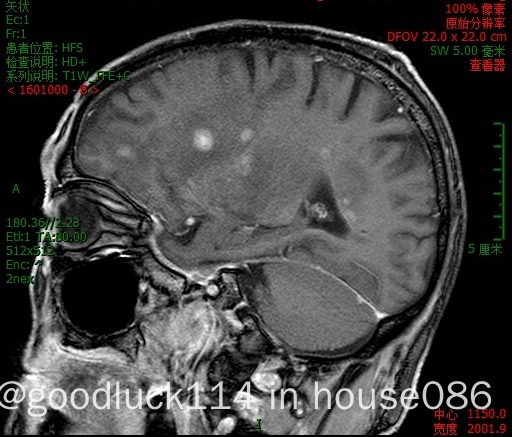

高龄取不了病理,医院做不了pet-ct,做了头颅ct和mri,发现颅内占位性病变,怀疑原发或转移,但胸部ct腹部ct和肿瘤标志物都没有明显异常,也没有除神经系统外其他系统的症状,mri增强结果不像是胶质瘤,高度怀疑是原发性中枢淋巴瘤。